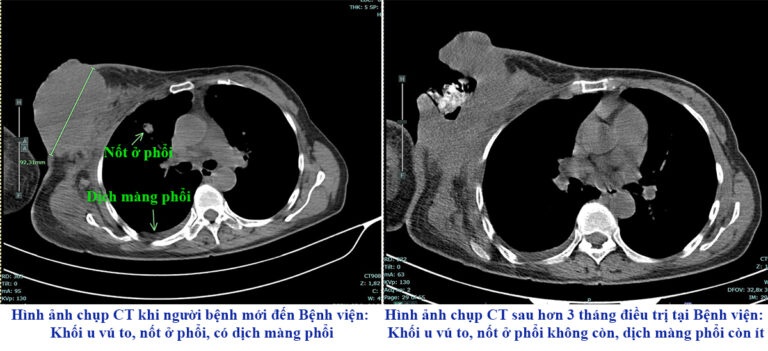

Hình ảnh chụp CT trước và sau điều trị của người bệnh. Ảnh: BVCC.

Theo bác sĩ Vĩnh, dù đã có nhiều cảnh báo về sự nguy hiểm của các phương pháp truyền miệng, không có cơ sở khoa học nhưng vẫn có không ít người bệnh đặt niềm tin vào tác dụng "thần kỳ" của những phương pháp này. Đáng tiếc, người bệnh đã từ chối cơ hội điều trị bằng y học hiện đại, khiến bệnh tiến triển nặng hơn.